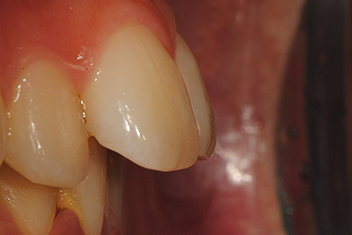

앞니 돌출 해소 케이스2

치료 기간12개월

경미한 앞니 돌출을 투명교정으로 빠르게 개선